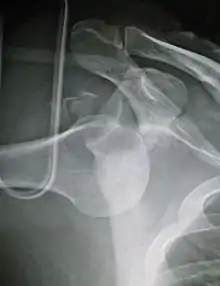

In over 95% of shoulder dislocations, the humerus is displaced anteriorly.[6] In most of those, the head of the humerus comes to rest under the coracoid process, referred to as sub-coracoid dislocation. Sub-glenoid, subclavicular, and, very rarely, intrathoracic or retroperitoneal dislocations may also occur.[7]

Anterior dislocations are usually caused by a direct blow to, or fall on, an outstretched arm. The person typically holds his/her arm externally rotated and slightly abducted.

An anterior dislocation of the shoulder

Anterior dislocation of the right shoulder. AP X ray